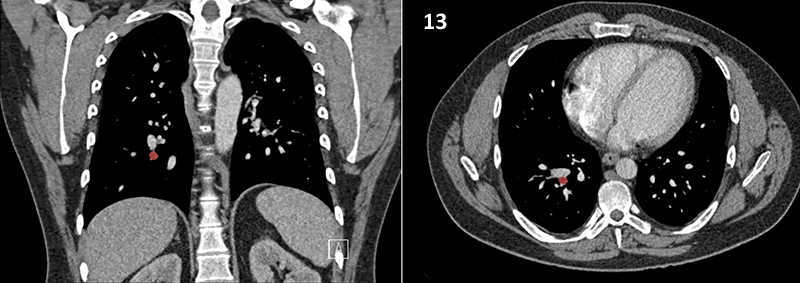

Nodal zones and stations according to the International Association for the Study of Lung Cancer (IASLC) node map.

Table (above): Nodal zones and stations according to the International Association for the Study of Lung Cancer (IASLC) node map. (Source: 1,2) *Depends on the side of the tumour.